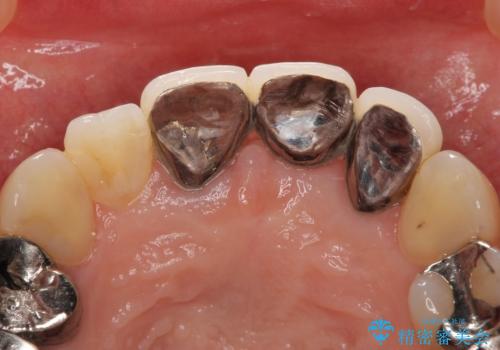

- 前歯のブリッジが不自然で気に入らないことを主訴に来院された患者様です。

前歯のレジン前装冠(保険内)によるブリッジは、金属で裏打ちされており透明感がなく不自然で、ポンティックも必要以上に長く作られていました。

古いブリッジと金属の土台を除去し、ファイバーコア(金属を使わない強くてしなやかな土台)を植立したのち、オールセラミックのブリッジによる補綴治療を行いました。。